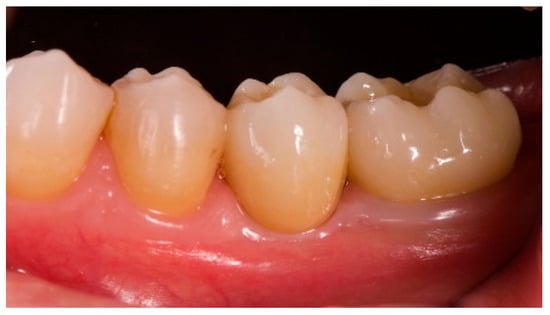

- The aesthetic evaluation was performed according to the pink aesthetic score (PES) on the vestibular and occlusal pictures taken including at least one adjacent tooth per side. The values were assessed at 6 and 12-months after loading follow-up examinations (18-months follow-up) [14] Seven variables (mesial papilla, distal papilla, soft-tissue level, soft-tissue contour, alveolar process deficiency, soft-tissue color and texture) were assessed with a 2-1-0 score (2 being best and 0 being poorest) by the same blinded dentist.

| PES (mm) | 8.2 ± 0.8 (95% CI 7.7–8.7) | 12.0 ± 0.7 (95% CI 11.5–12.5) |